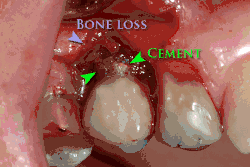

Зубной цемент под десной вызывает периимплантит и повреждение имплантата.